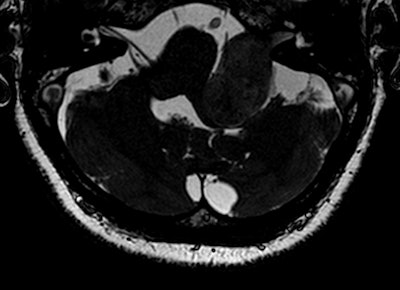

High-resolution T2-weighted (above) and enhanced T1-weighted (below) images of large intra- and extrameatal vestibular schwannoma. All images courtesy of Dr. Francesca Pizzini."Gadolinium-based contrast agents increase the relaxation rate of water protons in the region where they distribute, thus providing relevant information on pathologies, involving changes in the vascular density and permeability and structural differences," she said. "Unenhanced sequences available are not currently providing comparable and alternative structural details."